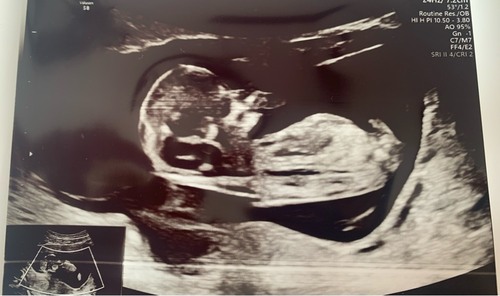

Wat denken jullie? 11+5

Nog eentje

En deze :)

Ik denk jongen